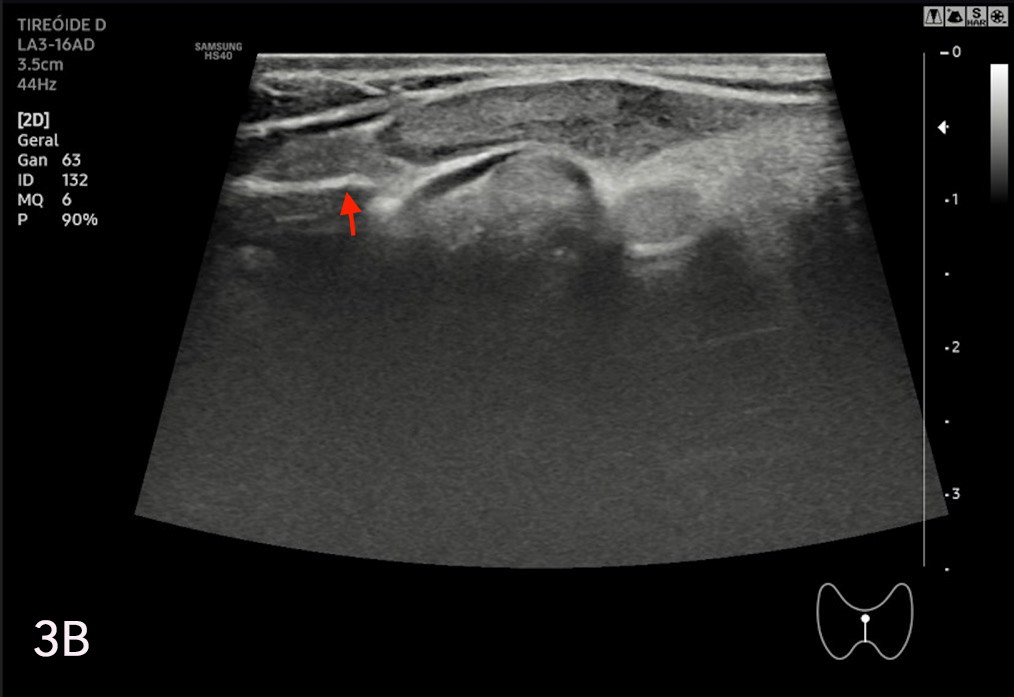

La eco estructura es homogénea, los márgenes son regulares y presenta una cápsula ecogénica, su vascularización es escasa. El rango de referencia para una tiroides normal es de entre cinco y diez vasos visibles dentro de la exploración de cada lóbulo valorado con Doppler color2. Se ha descripto que hasta un 50% de los individuos presentan lóbulo piramidal (Figura 3a y 3b). Este sector, en general, es similar en ecogenicidad, homogeneidad y vascularización al istmo y los lóbulos. En la superficie posterior de los lóbulos tiroideos, especialmente en el segmento inferior, puede visualizarse el tubérculo de Zuckerkandl, un ejemplo de este se puede observar en la figura 4a y 4b. Este es un tabique hiperecogénico fibroso que a menudo genera sombra posterior. Se forma por la extensión del tejido tiroideo de las áreas laterales de los lóbulos hacia el sector posterior, y a menudo exhibe una disminución de la ecogenicidad detrás del mismo. Este proceso puede imitar una lesión tiroidea o paratiroidea y causar dificultades en la interpretación2.